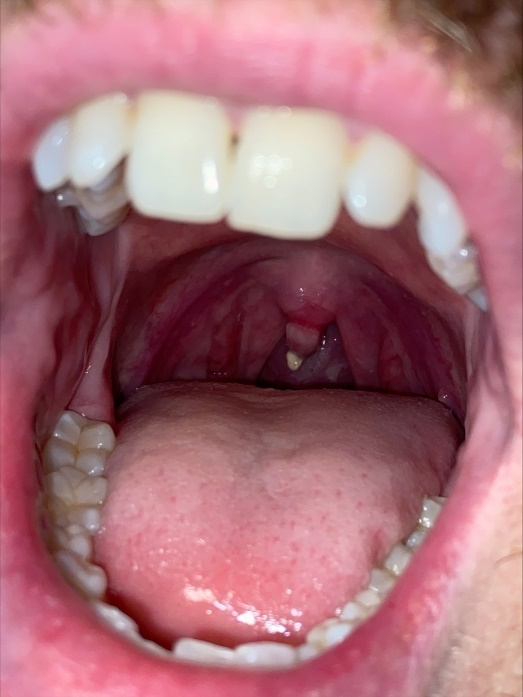

On post-operative day (POD) 4, the patient reported a sore throat, which had persisted since extubation on POD 0. He did not report any dysphagia, odynophagia, hoarseness, or dyspnea. On exam, his uvula was edematous with an ulcerated tip. There was no tonsillar enlargement, exudates, other oral lesions, or cervical lymphadenopathy (Figure 1). He was afebrile with normal vital signs and no leukocytosis. The case was discussed with Otolaryngology, who felt his symptoms were likely due to uvular necrosis related to his recent intubation. Conservative management was recommended, and he was prescribed throat lozenges and phenol spray. His sore throat and uvular edema gradually improved with these measures. By POD 8, the previously seen ulceration on his uvula was no longer appreciated (Figure 2). He was discharged to an acute rehabilitation unit to continue physical therapy.